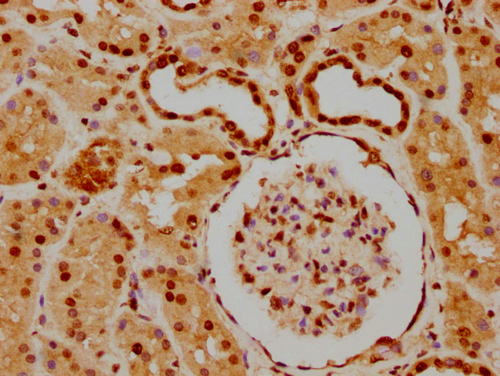

IHC image of CSB-PA010403PA05nforHU diluted at 1:20 and staining in paraffin-embedded human kidney tissue performed on a Leica BondTM system. After dewaxing and hydration, antigen retrieval was mediated by high pressure in a citrate buffer (pH 6.0). Section was blocked with 10% normal goat serum 30min at RT. Then primary antibody (1% BSA) was incubated at 4°C overnight. The primary is detected by a biotinylated secondary antibody and visualized using an HRP conjugated SP system.